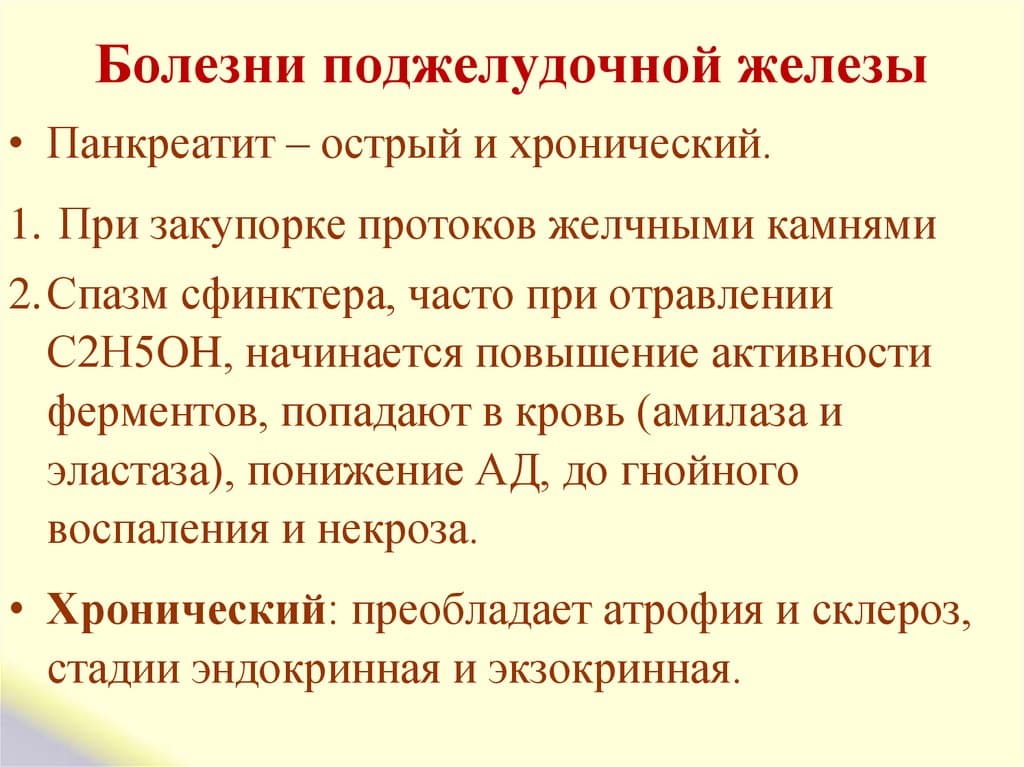

Как лечить – скажет врач. Самолечение здесь может только навредить. Боли в поджелудочной железе говорят о том, что в ней началось воспаление. Такое заболевание называется панкреатит. Для его начала должны быть весомые причины, чтобы в поджелудочной образовалось воспаление.

Панкреатит хронической формы дает меньше боли, чаще всего после погрешности в еде. Его опасность заключается в развитии опухоли самой ПЖ, отечности соседних тканей. В это время важно не пропустить рост злокачественных новообразований.

При повторяющихся приступах острый панкреатит переходит в хроническую форму. Боли проявляются после еды, если же аппетита нет, и человек ничего не ест, то боли не появляются вовсе. Зачастую больной ощущает признаки токсикоза, отвращение к некоторым продуктам.

Причины воспаления ПЖ

- употребление алкогольных напитков;